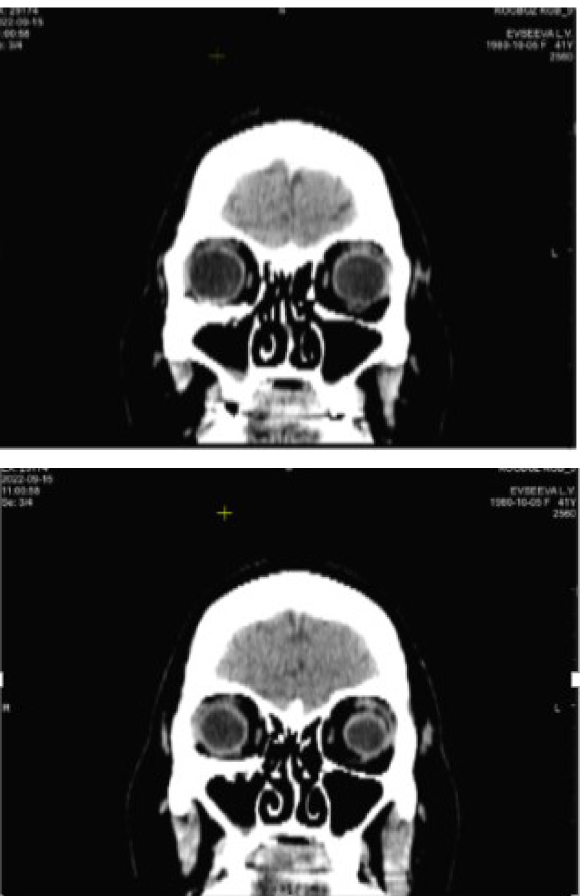

На момент обращения выявлен парез лицевого нерва, лагофтальм 5 мм, ретракция верхнего века 2 мм, край нижнего века располагается по нижнему лимбу, стойкое помутнение роговицы в нижней трети. В первичной позиции OD отклонен вверх-кнаружи на 2–3 градуса по Гиршбергу. Подвижность глазного яблока кверху, кнутри и книзу ограничена (рис. 8).

По данным КТ сохраняется расширение объема правой орбиты за счет смещения нижне-внутренней стенки до 10 мм на границе задней трети. Высота нижней стенки локально восстановлена за счет узкого костного трансплантата, расположенного аксиально на границе наружной трети (рис. 9).

Рис. 9. Компьютерная томография орбит до операции. Клинический пример 3